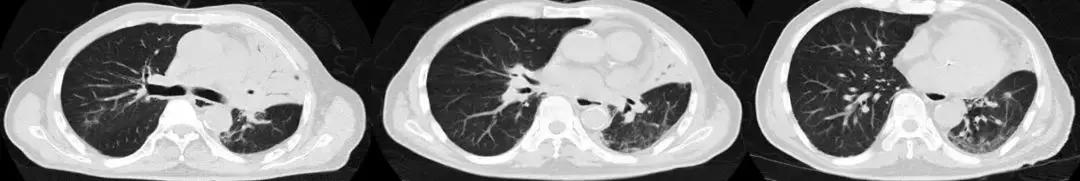

男,67岁,急性病程;发病前有旅游病史;主诉:发热、干咳伴呼吸困难2天,加重1天;查体:体温38.3℃,心率96次/分, 呼吸35次/分,血压98/63mmHg,SpO2 88%(FiO20.37),急性病容,呼吸急促,左肺呼吸音粗,右下肺呼吸音减弱,双下肺可闻及湿啰音;肺部CT示双下肺渗出、实变影,动脉血气分析提示I型呼吸衰竭。

2017-9-26

2017-9-29

支气管镜检查示

双侧气管黏膜充血,可见大量脓黄痰,左下肺基底段灌注生理盐水50ml,回收20ml,送检细菌和真菌涂片、培养;7项呼吸道病原体;EB病毒核酸、巨细胞病毒核酸;抗酸杆菌涂片及染色、结核分枝杆菌鉴定及药敏。最终结果回报:H1N1和金黄色葡萄球菌(MSSA)。降级抗生素为阿莫西林克拉维酸钾联合奥司他韦抗病毒治疗,患者症状好转出院。

经验教训

甲型流感病毒感染后可能出现继发细菌(肺炎链球菌、金黄色葡萄球菌、流感嗜血杆菌等)和曲霉感染,一定注意病原检测,不要过度依赖于强大的抗细菌药物。